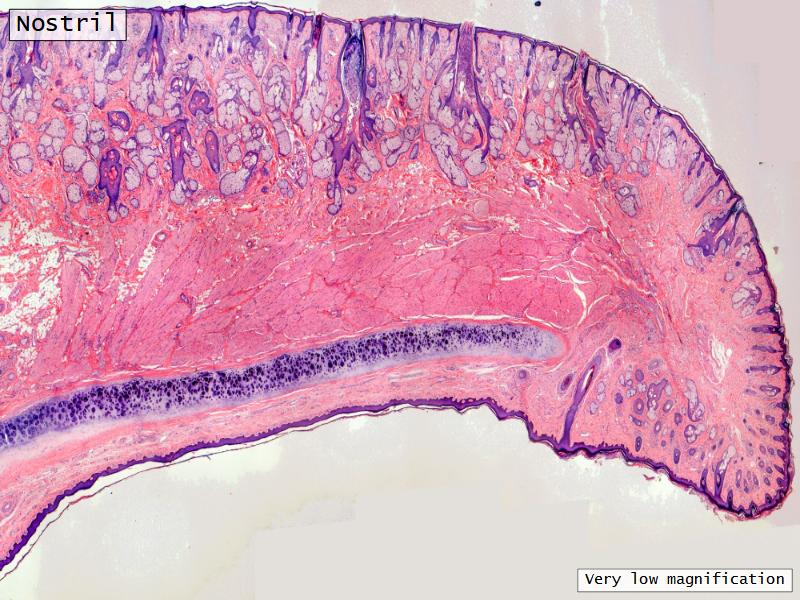

Slides: Respiratory System

- Slide 71: Nostril

Nostril